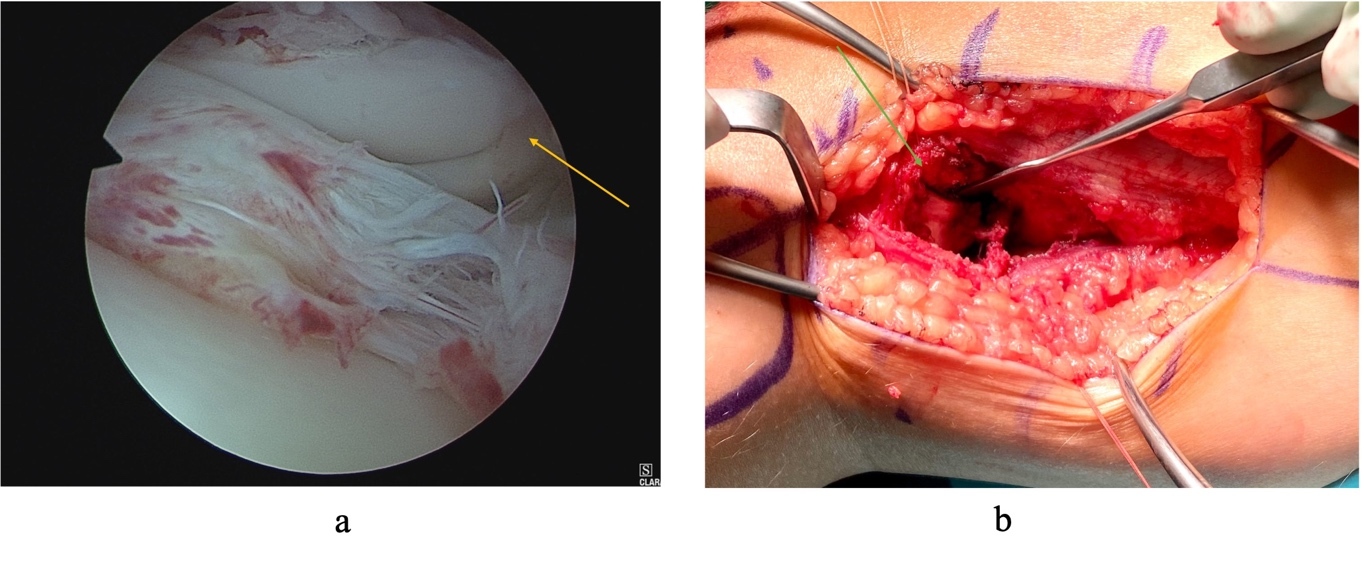

Arthroscopy revealed an irreducible bucket handle tear of the lateral meniscus. Visualization of the Busch-Hoffa fracture was not possible at this stage (Fig 3). A lateral approach to the knee was performed utilizing the interval between biceps femoris and the iliotibial band. Care was taken to protect the common peroneal nerve. The posterolateral capsule was exposed and an arthrotomy was performed. Capsular stay sutures aided retraction and exposure (Fig 3). The fracture fragment was identified and it was noted that a partially torn popliteus tendon was incarcerated in the fracture site (Fig 4). The popliteus tendon was removed from the fracture site and the fracture fragments were reduced anatomically. Two 2mm headless compression screws were used to stabilize the fracture. Subsequently, arthroscopy was resumed, and reduction of the lateral meniscal bucket handle tear was now possible. This was repaired with two all-inside sutures.